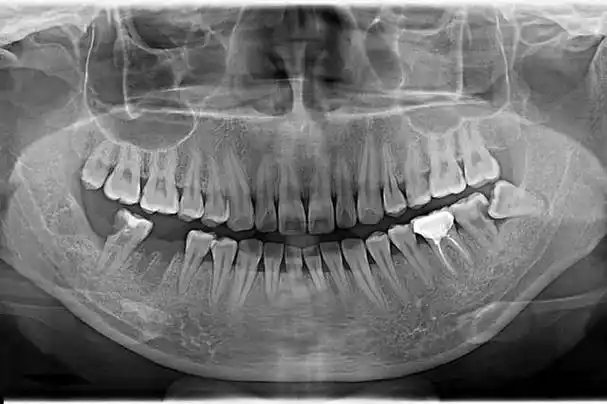

什么是口腔全景片